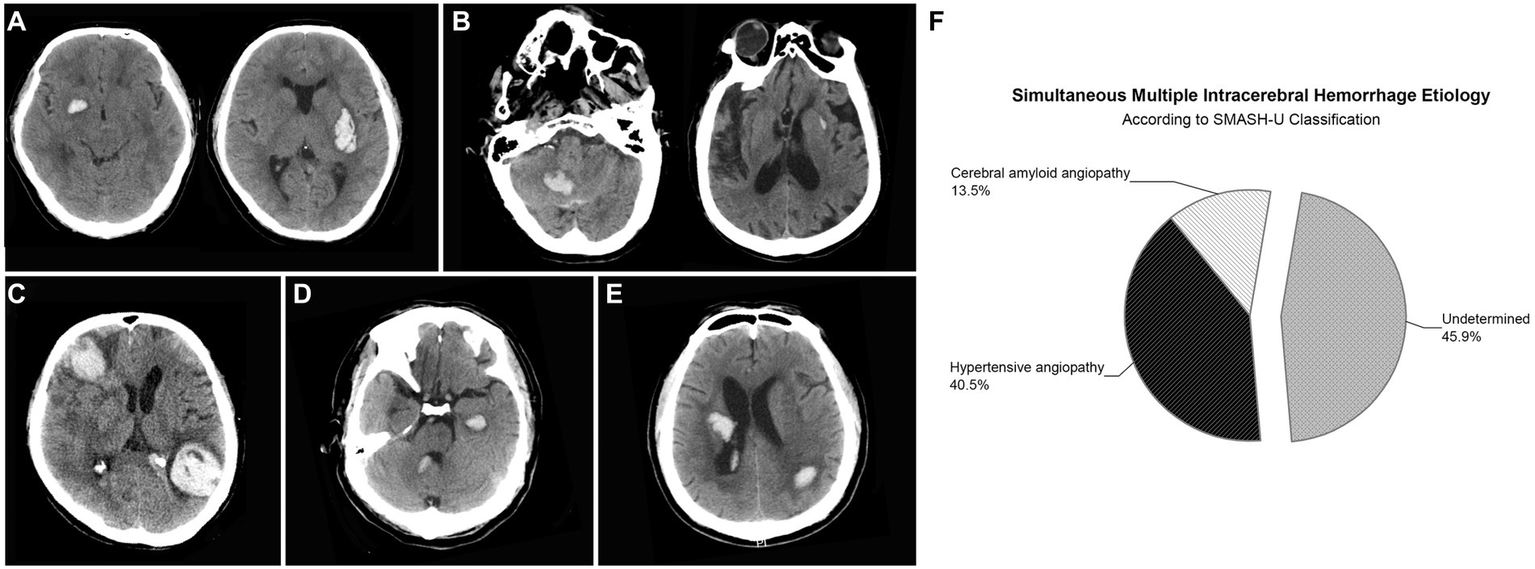

SMICH was identified in 37 (6.2%) participants according to the criteria and the representative images were presented in Figure 2. There were 76 discrete ICH lesions in the SMICH group: 35 patients (94.6%) had two hematomas, while the remaining had three. The topographic distribution was as follows: 17 lenticular nuclei, 14 thalami, 7 internal capsules, 4 caudate nuclei, 10 temporal lobes, 6 frontal lobes, 6 occipital lobes, 4 parietal lobes, 6 cerebella, and 2 pontes. Based on MRI examination, no new hematoma occurred compared to the baseline image.

Figure 2

Representative examples of patients with simultaneous multiple intracerebral hemorrhage (SMICH). According to SMASH-U classification, patients who had ICH restricted to deep (A) or infratentorial (B) regions with pre-ICH hypertension were classified as hypertensive angiopathy; Cerebral amyloid angiopathy (CAA) was defined by patients aged ≥55 with lobar hematoma (C). Patients with co-existing lobar and deep/infratentorial ICH were classified as undetermined-SMICH (D,E). Cerebral amyloid angiopathy (n = 5 [13.5%]) and hypertension (n = 15 [40.5%]) were common classifications, whereas 17 (45.9%) patients with primary SMICH had an undetermined etiology (F).

According to the SMASH-U classification, amyloid angiopathy (n = 5 [13.5%]) and hypertension (n = 15 [40.5%]) were the common etiologies, whereas 17 (45.9%) patients with primary SMICH had an undetermined etiology.